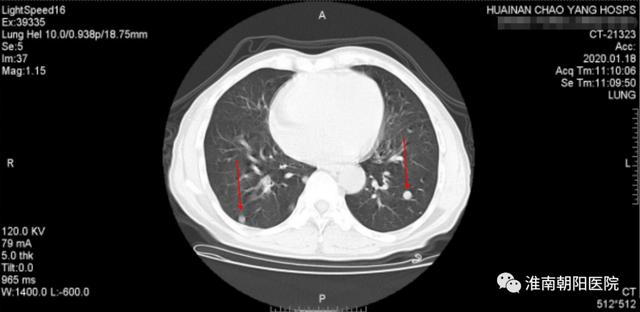

随后患者张大爷又接受两轮化疗,身体状况逐渐变好!但好景不长,肿瘤这个狡猾的家伙居然耐药了,在 12 月份的胃镜检查中我们意外地发现食管内仍然有残存病灶,经过全体专家的会诊后更换了化疗方案治疗,但今年 1 月份复查的时候,医生发现两肺多发转移,病情有进展了!

(图中红色箭头所指的就是肺内的转移灶)